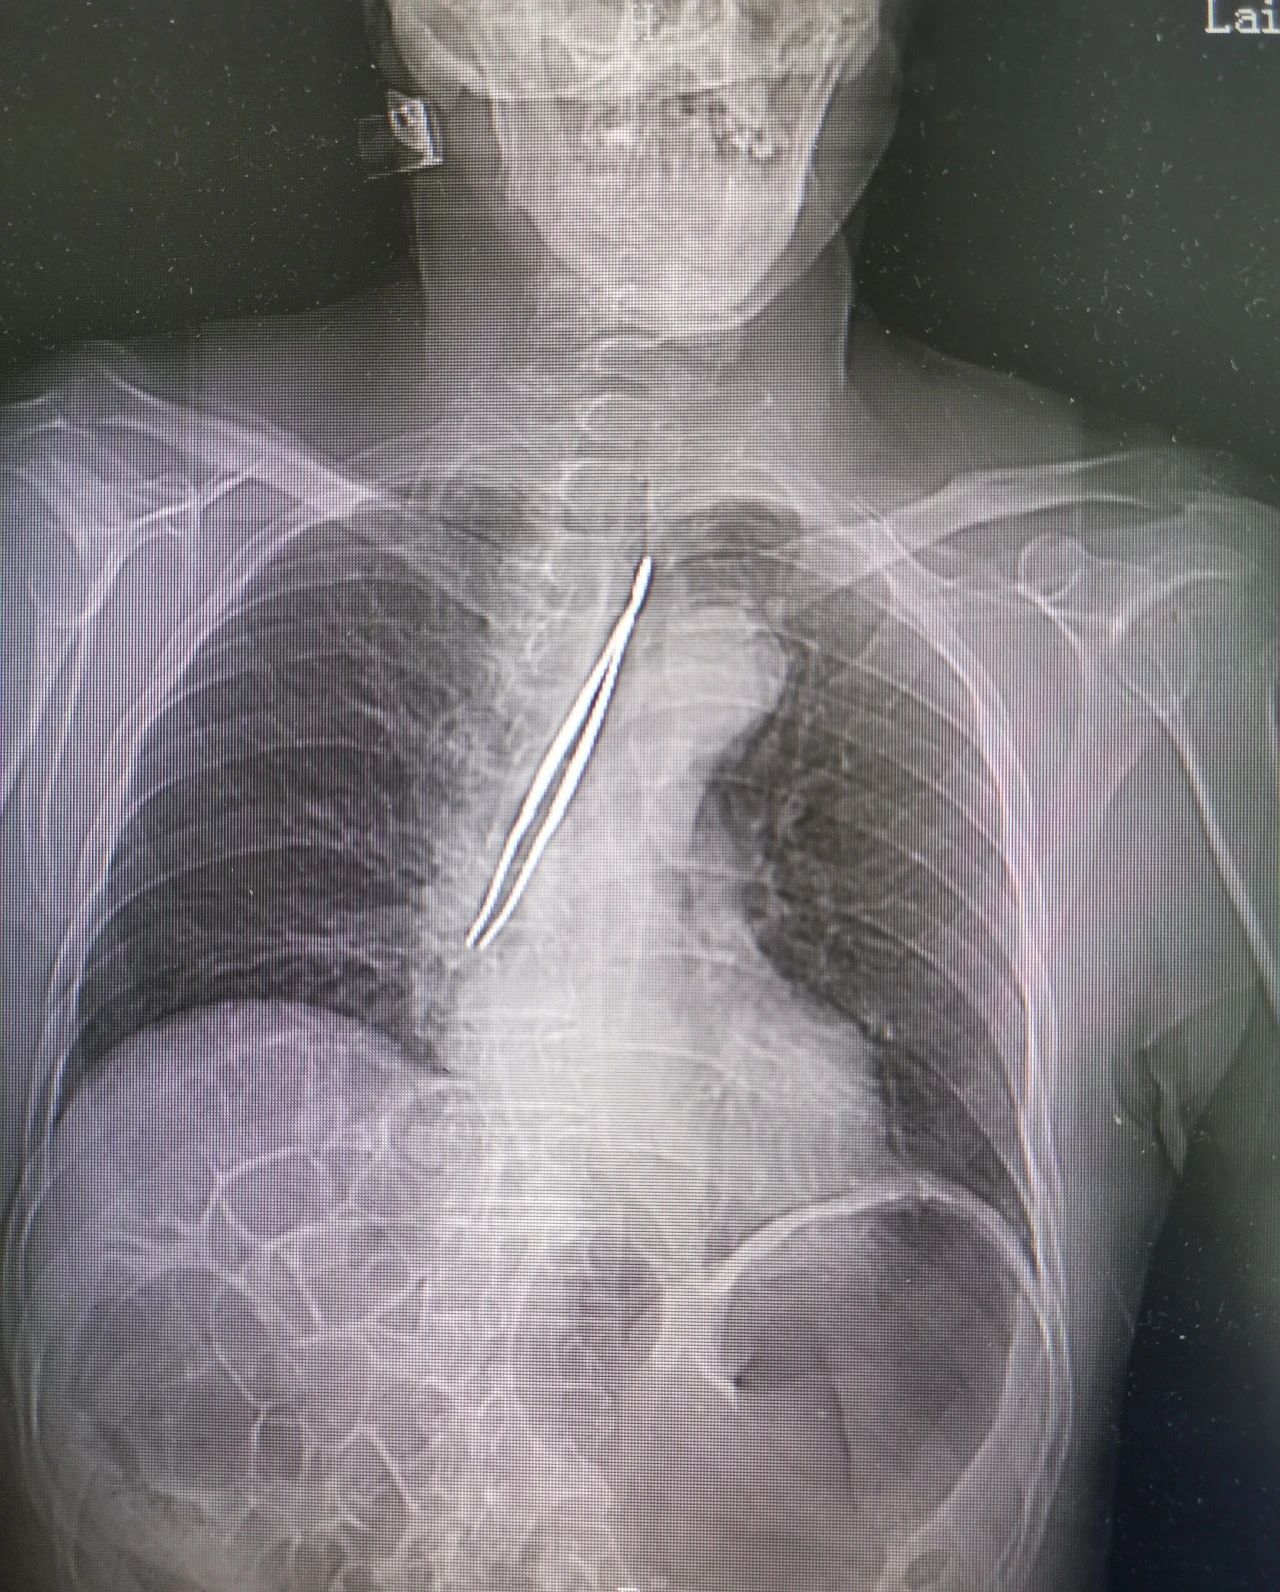

据了解,该患者喉癌术后10余年,气管切开状态,今日在家用自己购买的镊子取出切口处分泌物时,镊子不慎掉入气管内。此时常规检查已无法窥见异物,患者时有咳嗽,田凯主任当机立断,为患者开通绿色通道,行紧急CT检查,同时联系相关科室做好配合准备。CT可见,气管内一镊子形状异物,前端已进入右侧主支气管,需立即取出。

重症医学科主任邹贻武、呼吸与危重症医学科主任曾圣凯参与会诊后,决定立即为邹大爷行急诊气管异物取出术。术中,重症医学科主任邹贻武严密监测患者生命体征,呼吸与危重症医学科主任曾圣凯持纤支镜锁定异物位置,五官科主任田凯经气管切口取出异物。整个手术过程不足10分钟,距患者来院不足一小时。